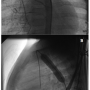

Catheterization and angioplasty data. The peak-to-peak systolic pressure gradient across the coarctation site was measured before and after angioplasty procedures. The diameters of the coarctation site were recorded. Most measurements were obtained from the systolic frames and lateral projections (Figure 1).